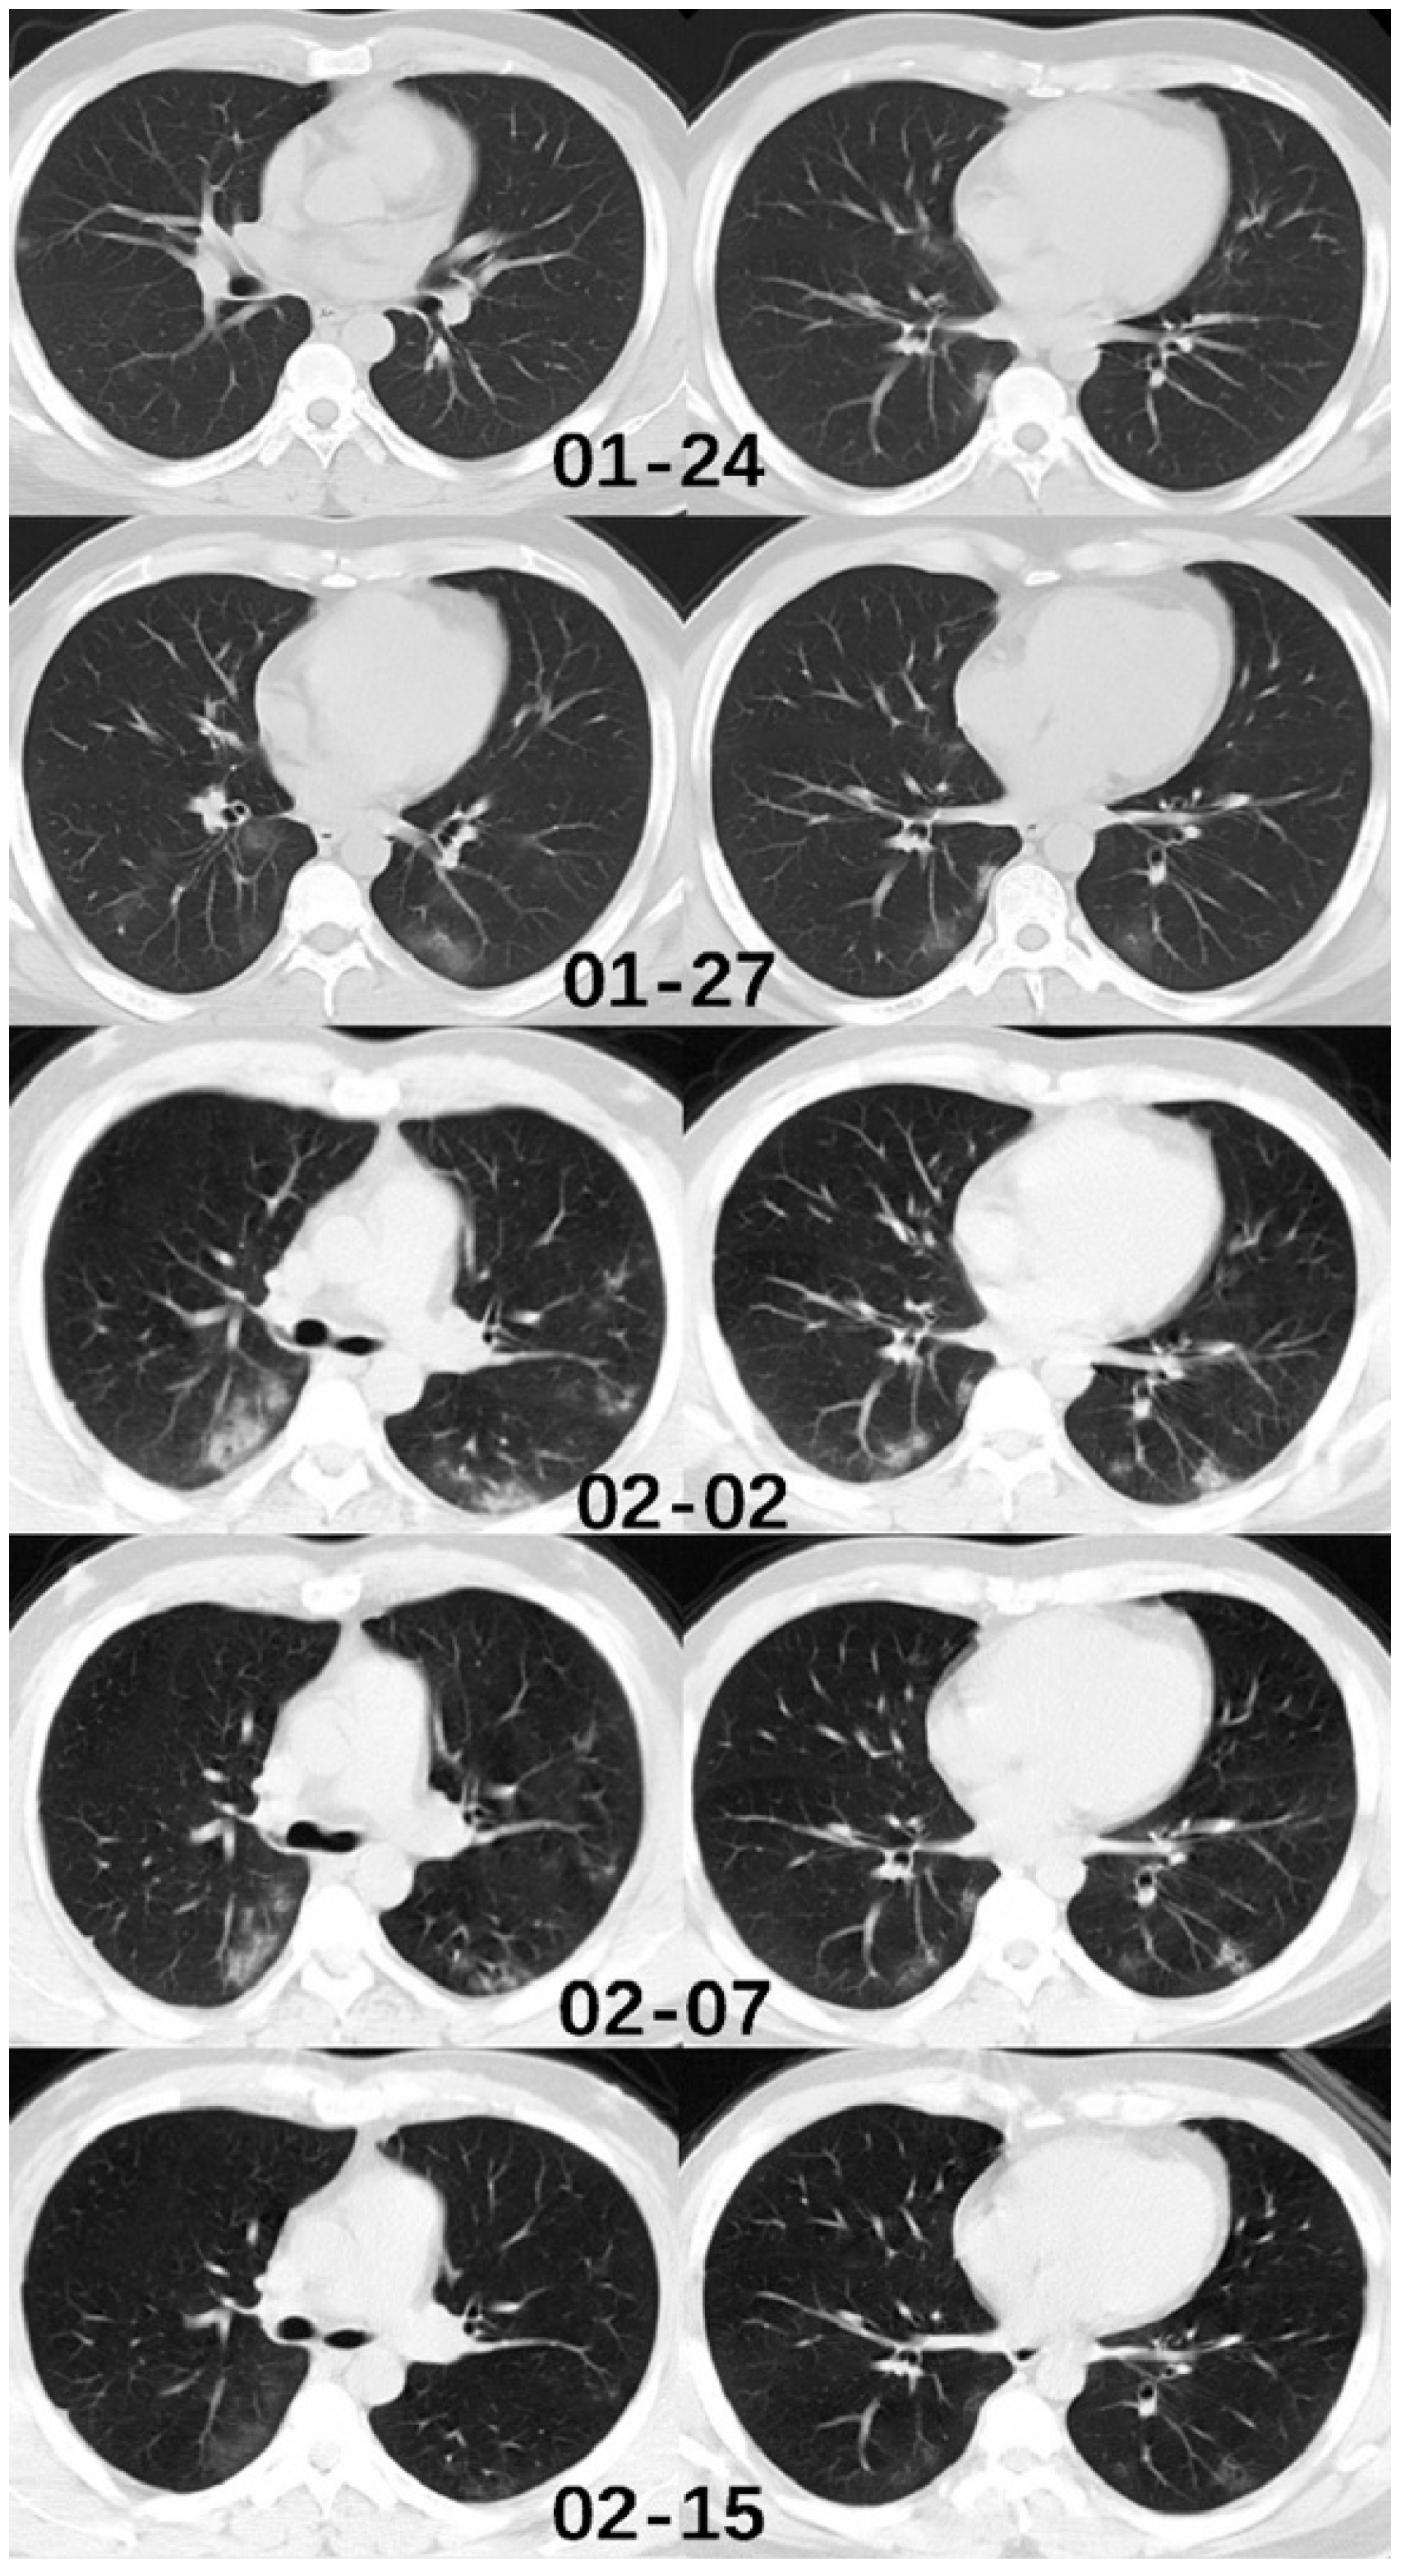

- Shi, H.; Han, X.; Jiang, N.; Cao, Y.; Alwalid, O.; Gu, J.; Fan, Y.; Zheng, C. Radiological findings from 81 patients with COVID-19 pneumonia in Wuhan, China: A descriptive study. Lancet Infect. Dis. 2020, 20, 425–434. [Google Scholar] [CrossRef]

- Ai, T.; Yang, Z.; Hou, H.; Zhan, C.; Chen, C.; Lv, W.; Tao, Q.; Sun, Z.; Xia, L. Correlation of chest CT and RT-PCR testing in coronavirus disease 2019 (COVID-19) in China: A report of 1014 cases. Radiology 2020, 200642. [Google Scholar] [CrossRef]

- Fang, Y.; Zhang, H.; Xie, J.; Lin, M.; Ying, L.; Pang, P.; Ji, W. Sensitivity of Chest CT for COVID-19: Comparison to RT-PCR. Radiol. 2020, 200432. [Google Scholar] [CrossRef] [PubMed]

- Caruso, D.; Zerunian, M.; Polici, M.; Pucciarelli, F.; Polidori, T.; Rucci, C.; Guido, G.; Bracci, B.; De Dominicis, C.; Laghi, A. Chest CT Features of COVID-19 in Rome, Italy. Radiol. 2020, 201237. [Google Scholar] [CrossRef]

- Li, Y.; Xia, L. Coronavirus disease 2019 (COVID-19): Role of chest CT in diagnosis and management. Am. J. Roentgenol. 2020, 214, 1280–1286. [Google Scholar] [CrossRef] [PubMed]

- Yang, W.; Cao, Q.; Qin, L.; Wang, X.; Cheng, Z.; Pan, A.; Dai, J.; Sun, Q.; Zhao, F.; Qu, J. Clinical characteristics and imaging manifestations of the 2019 novel coronavirus disease (COVID-19): A multi-center study in Wenzhou city, Zhejiang, China. J. Infect. 2020, 80, 388–393. [Google Scholar] [CrossRef] [PubMed]